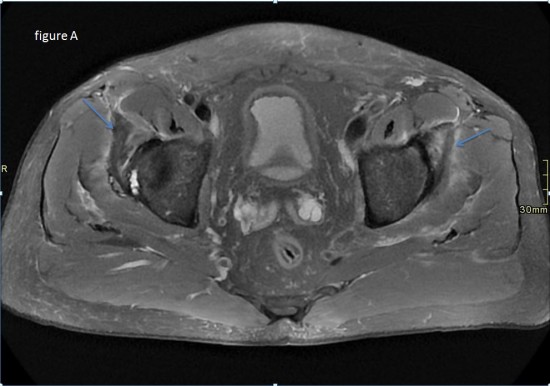

Une anomalie des membres caracterisee par labsence congenitale dun membre a partir du coude. Tumeurs pseudo tumeurs thrombose veineuse ulnaire du poignet irm.